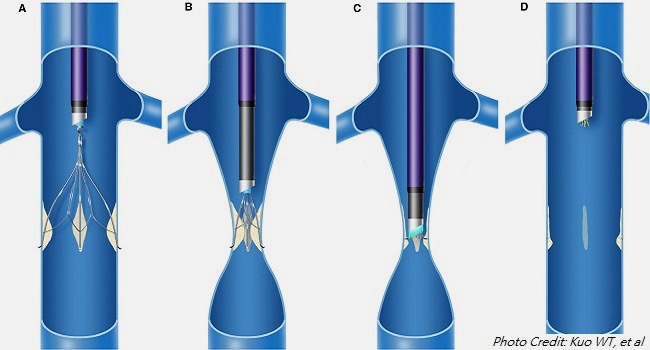

گامهای اصلی روش قرارگیری

- انتخاب دسترسی وریدی:

• ترجیحاً ورید ژوگولار داخلی راست (در گردن) یا ورید فمورال (در کشاله ران).

• دسترسی راست اولویت دارد چون مسیر مستقیمتری به IVC دارد.

• پوست با مواد ضدعفونی تمیز میشود، بیحسی موضعی تزریق میشود و برش کوچکی (کمتر از ۱ سانتیمتر) ایجاد میشود. - قرار دادن وایر راهنما (guidewire):

• با سوزن، ورید پانکچر میشود (اغلب تحت اولتراسوند برای دقت).

• وایر نازک وارد ورید میشود و تحت فلوروسکوپی به IVC هدایت میشود. - ونوگرافی (Cavography):

• کاتتر چندسوره وارد میشود.

• ماده حاجب تزریق میشود تا آناتومی IVC، قطر آن، موقعیت وریدهای کلیوی (renal veins) و وجود لخته بررسی شود.

• موقعیت ایدهآل فیلتر: درست زیر وریدهای کلیوی (infrarenal) برای جلوگیری از انسداد

- قرار دادن sheath تحویل فیلتر ivc قلبی:

• sheath (لوله بزرگتر) روی وایر پیشرفته میشود تا به موقعیت مورد نظر برسد. - باز کردن (Deployment) فیلتر ivc قلبی:

• فیلتر فشردهشده داخل sheath推進 میشود.

• sheath عقب کشیده میشود تا فیلتر باز شود و با قلابها یا پاها به دیواره IVC بچسبد.

• تکنیکهای پیشرفته مانند Over-the-Wire (OTW) برای کاهش tilt (کج شدن فیلتر) استفاده میشود.

- بررسی نهایی فیلتر ivc قلبی:

• تصویر فلوروسکوپی برای چک موقعیت، tilt (باید کمتر از ۱۵ درجه)، migration یا perforation.

• گاهی ونوگرام پس از قرارگیری.

- پایان روش فیلتر ivc قلبی:

• کاتتر و sheath خارج میشود.

• محل دسترسی با فشار دستی بسته میشود (۵-۱۰ دقیقه).

• بانداژ گذاشته میشود.

• بیمار ۲-۴ ساعت استراحت میکند (اگر دسترسی فمورال، درازکش).